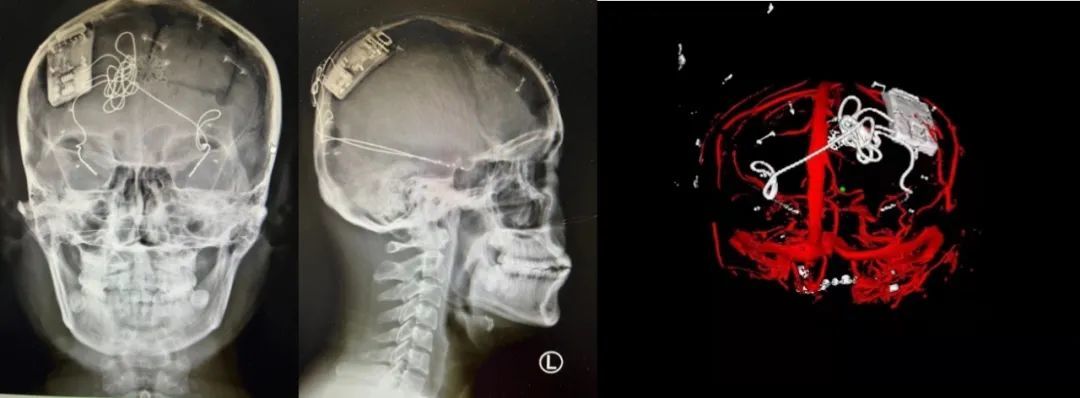

本次手術過程順利,術中刺激器各項指標均工作正常,術后重建顯示電極位置精準,腦電信號清晰?;颊邽槟行?,入院后診斷為雙側顳葉癲癇,此類癲癇為開顱手術的相對禁忌癥,在藥物無法控制的情況下,傳統治療效果欠佳 。

術前經過宣武醫(yī)院癲癇多學科專家團隊詳細的臨床評估,包括視頻腦電監(jiān)測、頭顱磁共振及三維 CT 掃描、腦核醫(yī)學檢查等,全面評估了患者病情及致癇灶定位情況。

由于患者臨床診斷為雙側顳葉癲癇伴海馬硬化,無法通過致癇灶切除等傳統外科手術方式獲益,決定進行閉環(huán)反應性神經刺激系統植入手術治療。并根據閉環(huán)神經刺激技術特點,為患者“量身定制”植入方案,尤其是電極植入位點和脈沖發(fā)生器固定部位等,為手術的順利實施奠定了良好基礎。

團隊根據術前計劃,在手術機器人輔助下完成雙海馬長軸電極及 IPG 植入,術后重建顯示電極位置精準,腦電信號清晰。術后第二天,患者即下床活動,身體狀況恢復良好。